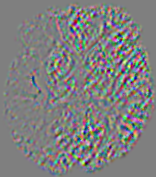

4.3.1 Advection Imaging via Advection-Diffusion

Slice #1Slice #2Slice #3Slice #4Slice #5Slice #6𝐕gt𝟐subscriptnormsuperscript𝐕gt2\|\bf{V}^{\text{gt}}\|_{2}Refer to captionRefer to captionRefer to captionRefer to captionRefer to captionRefer to caption𝐕est𝟐subscriptnormsuperscript𝐕est2\|\bf{V}^{\text{est}}\|_{2}Refer to captionRefer to captionRefer to captionRefer to captionRefer to captionRefer to captionRefer to caption1.51.51.51.21.21.20.90.90.90.60.60.60.30.30.30.00.00.0(mm/s)𝑚𝑚𝑠(mm/s)Destsuperscript𝐷estD^{\text{est}}Refer to captionRefer to captionRefer to captionRefer to captionRefer to captionRefer to captionRefer to caption0.0150.0150.0150.0120.0120.0120.0090.0090.0090.0060.0060.0060.0030.0030.0030.0000.0000.000(mm2/s)𝑚superscript𝑚2𝑠(mm^{2}/s)

Figure 14: PIANO identifiability testing: advection imaging via advection-diffusion. Top row shows 𝐕gt2subscriptnormsuperscript𝐕gt2\|{\bf{V}}^{\text{gt}}\|_{2} used for simulating ground truth pure advection. Rows below show the estimated 𝐕est2subscriptnormsuperscript𝐕est2\|{\bf{V}}^{\text{est}}\|_{2} and Destsuperscript𝐷estD^{\text{est}} on corresponding slices. Note that the plotted value scale for Destsuperscript𝐷estD^{\text{est}} is 0.01 of that for 𝐕gt2subscriptnormsuperscript𝐕gt2\|{\bf{V}}^{\text{gt}}\|_{2} and 𝐕est2subscriptnormsuperscript𝐕est2\|{\bf{V}}^{\text{est}}\|_{2}.

We use the same ‘Advection Imaging’ simulation of Sec. 4.2.1 as the concentration dataset for PIANO. However, instead of modeling pure advection (Eq. 15), we let PIANO estimate both velocity 𝐕estsuperscript𝐕est{\bf{V}}^{\text{est}} and diffusivity Destsuperscript𝐷estD^{\text{est}} via the advection-diffusion PDE (Eq. 2) underlying the proposed PIANO model. Fig. 14 shows the estimated 𝐕est2,subscriptnormsuperscript𝐕est2\|{\bf{V}}^{\text{est}}\|_{2}, and Destsuperscript𝐷estD^{\text{est}} fields for one patient. Although PIANO has the freedom to estimate both a velocity and a diffusivity field from pure advection, PIANO differentiates well between advection and diffusion: the estimated 𝐕est2subscriptnormsuperscript𝐕est2\|{\bf{V}}^{\text{est}}\|_{2} successfully reproduces the ground truth 𝐕gt2subscriptnormsuperscript𝐕gt2\|{\bf{V}}^{\text{gt}}\|_{2} governing the simulated advection process, just as it already did in the ‘Advection Imaging via Advection’ test (Fig. 12). More importantly, the estimated diffusivity Destsuperscript𝐷estD^{\text{est}} is orders of magnitudes smaller than 𝐕est2subscriptnormsuperscript𝐕est2\|{\bf{V}}^{\text{est}}\|_{2}, indicating the estimated diffusion is negligible compared to the estimated advection, which is highly consistent with the underlying pure advection of the simulated data.